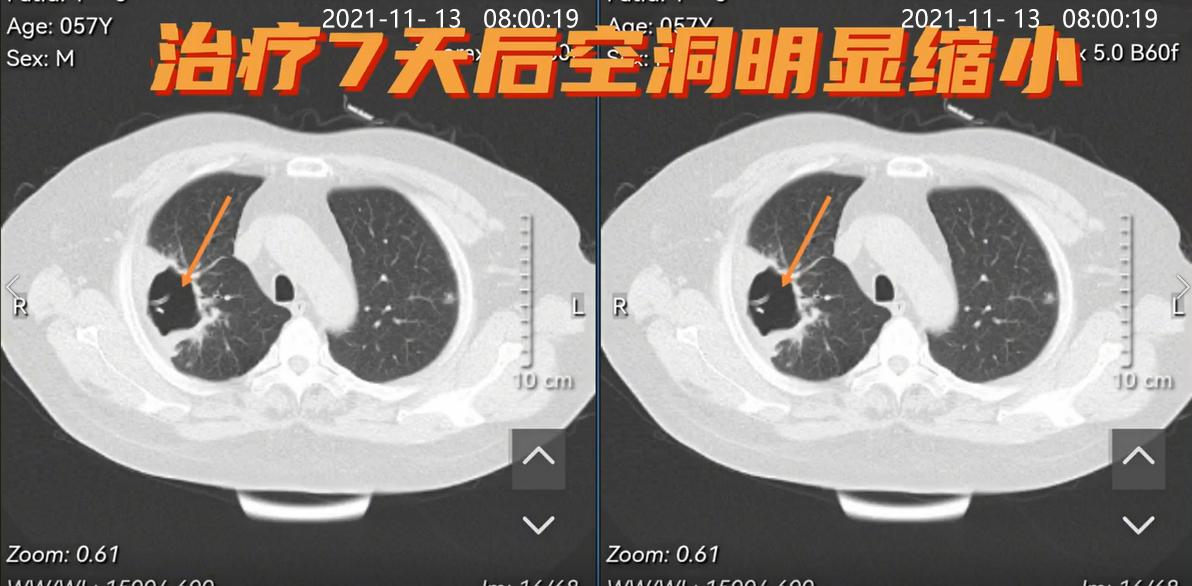

12月5日前往医院看病,经肺部CT检查后,发现肺里有一个巨大的洞,这个洞医学上称为“肺脓肿”,杨女士住院抗菌治疗结合脓液引流,治疗7天后空洞明显缩小。

杨女士治疗后CT空洞

肺脓肿在CT中的典型表现: 空洞大小不一、空洞可单发也可多发、空洞边缘光滑,合并感染时壁增厚而边缘模糊、可见中等或大量脓液。